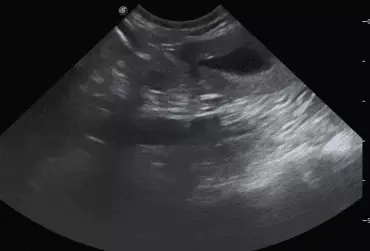

W literaturze opisano niewiele przypadków ciąż bliźniaczych jednokosmówkowych u suk. W trakcie wczesnej diagnostyki ultrasonograficznej ciąży u suki rasy whippet (chart angielski) zobrazowano pęcherz ciążowy, w którym znajdowały się dwa zarodki. Podczas badań kontrol­nych zarodki, a później płody wykazywały prawidłową organogenezę i żywotność. Ich rozwój przebiegał podobnie względem pozostałych ośmiu płodów. W 63. dniu ciąży wykonano zabieg cesarskiego cięcia i wydobyto dwa płody tej samej płci, o bardzo podobnym wyglądzie, z dwóch pęcherzy płodowych przyczepionych do jednego łożyska, oraz pozostałe osiem płodów.